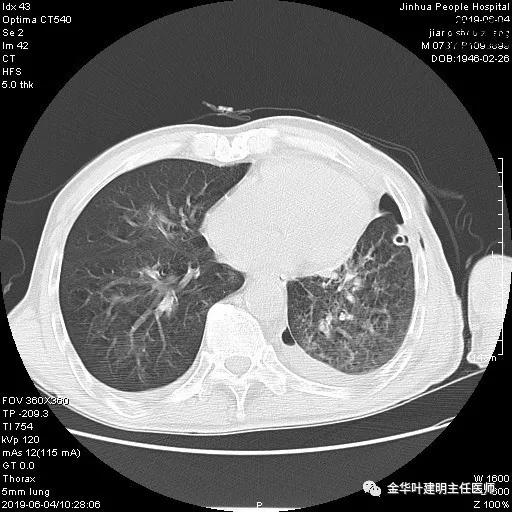

6.4上午:24小时引流出血性乳糜液1800毫升。是否再次手术进行右进胸胸导管结扎,抑或继续保守治疗非常纠结!压力非常大!!多方讨论会诊无法取得一致意见,但一般认为,引流量在1000毫升以上宜积极手术。情况与浙二医院范军强教授联系,请求指导,范教授认为左侧肺手术,损伤胸导管主干的机会较小,多数可保守治疗而愈。在他们的病例中,也有结扎胸导管后引流量仍无减少,效果并不能完全保证。建议可以考虑胸管夹管观察(因为淋巴管压力低,予以适当的压力,漏出量可能会明显减少),同时继续禁食,并静脉营养支持,引流管口可能会有渗液,关注更换敷料。与家属充分沟通后决定试夹管;这天血色素9.0 g/L;胸部CT复查示:

夹管情况下,于6.5复查胸片:

感觉左肺密度还可以,肺没有被全部压萎陷,积液有,但不是特别多。